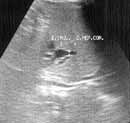

Таким образом, дооперационная диагностика кистозной трансформации желчевыводящих путей в настоящее время значительно улучшилась благодаря применению современных методов исследования. Однако, выбор оперативного метода лечения окончательно может быть произведен только во время операции, так как решающее значение в верификации диагноза имеют интраоперационные рентгеноконтрастные методы исследования, которые позволяют выявить кистозные расширения вне- и внутрипеченочных желчных протоков, степень и протяженность их дилятации, проходимость терминального отдела холедоха, рубцовые сужения печеночных протоков, билиопанкреатический рефлюкс. Поэтому всем больным после лапаротомии производилась интраоперационная холангиография и, на основании полученных данных решался вопрос о выборе метода хирургического лечения. Данная методика выполнена 10 пациентам (Рис. 3).

Рис. 3. Интраоперационная холангиография.